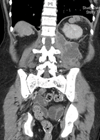

Retroperitoneal sepsis

Case 1 An 80-year-old woman presented with history of recurrent and recent cystitis, low grade pyrexia, abdominal and back pain, and pain on movement of the left hip which was observed to be flexed and externally rotated. What is the...